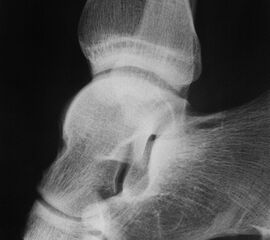

Aufnahmen Kalkaneus und USG

Broden-Aufnahme

Broden-Aufnahme Innenrotation

Indikation:

• Darstellung der dorsalen Facette des Subtalargelenks in verschiedenen Projektionen.

• Die Aufnahme wurde durch CT und DVT weitgehend abgelöst.

• Broden-Projektionen werden intraoperativ zur Beurteilung der Rekonstruktion der dorsalen Gelenkfacette bei Kalkaneusfrakturen verwendet.

Positionierung:

• Patient in Rückenlage, Fuß in Innenrotation (45°), Sprunggelenk im 90°-Winkel abgewinkelt, ggf. gelagert auf einem Schaumstoffkeil.

• Filmposition horizontal am Röntgentisch.

• Zentralstrahl verläuft je nach angefordeter Gradzahl 10°, 20°, 30°, und oder 40° caudo-cranial auf das untere Sprunggelenk.

Kennzeichen des Röntgenbildes:

• Gute Einsicht in den hinteren unteren Sprunggelenkabschnitt durch unterschiedliche Projektionen.

• Überlagerungsfreie Darstellung des Außenknöchels und der tibiofibularen Syndesmose.

Besondere Bemerkungen zum Beispielbild:

• Brodenaufnahme 10°.

• Initiale degenerative Veränderungen im Subtalargelenk.

• Impression der lateralen Gelenkfläche des Kalkaneus.

Zur Vollansicht und zum Lesen der Bildbeschreibung bitte das Bild anklicken.